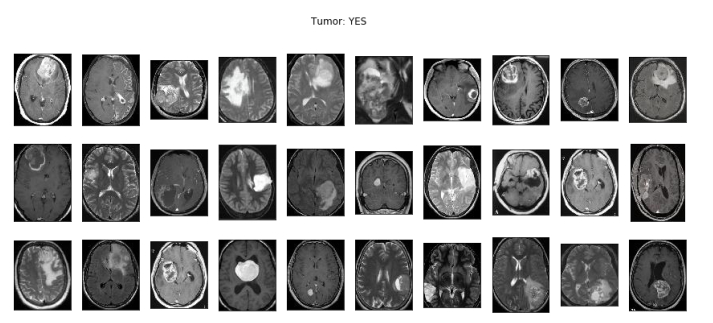

[46] R. Ranjbarzadeh, A. Keles, M. Crane, M. Bendechache, Comparative analysis of real-clinical MRI and BraTS datasets for brain tumor segmentation, CP887, IET, (2024), pp. 39–46.

[48] S. Suchitra, Parkinson disease prediction using deep learning algorithm, rp-9788770040723.217.

[55] R. Ranjbarzadeh, A. Caputo, E. B. Tirkolaee, S. J. Ghoushchi, M. Bendechache, Brain tumor segmentation of MRI images: A comprehensive review on the application of artificial intelligence tools, Comput. Biol. Med., 152 (2023), 106405. https://doi.org/10.1016/j.compbiomed.2022.106405 doi: 10.1016/j.compbiomed.2022.106405

[61] N. T. Sarshar, S. Sadeghi, M. Kamsari, M. Avazpour, S. J. Ghoushchi, R. Ranjbarzadeh, Advancing brain MRI images classification: Integrating VGG16 and ResNet50 with a Multi-verse optimization method, (2024).

[62] R. Ranjbarzadeh, A. B. Kasgari, S. J. Ghoushchi, S. Anari, M. Naseri, M. Bendechache, Brain tumor segmentation based on deep learning and an attention mechanism using MRI multi-modalities brain images, Sci. Rep., 11 (2021), 10930. https://doi.org/10.1038/s41598-021-90428-8 doi: 10.1038/s41598-021-90428-8

[68] A. B. Kasgari, R. Ranjbarzadeh, A. Caputo, S. B. Saadi, M. Bendechache, Brain tumor segmentation based on zernike moments, enhanced ant lion optimization, and convolutional neural network in MRI images, in: Metaheuristics and Optimization in Computer and Electrical Engineering, Hybrid and Improved Algorithms, Springer, 2 (2023), pp. 345–366.

[73] R. Ranjbarzadeh, M. Crane, M. Bendechache, The impact of backbone selection in Yolov8 Models on brain tumor localization, Iran J. Comput. Sci., (2025), 1–23. https://doi.org/10.1007/s42044-025-00258-4 doi: 10.1007/s42044-025-00258-4

[75] R. Ranjbarzadeh, A. Keles, M. Crane, S. Anari, M. Bendechache, Secure and decentralized collaboration in oncology: A blockchain approach to tumor segmentation, IEEE, 2024, pp.1681–1686.